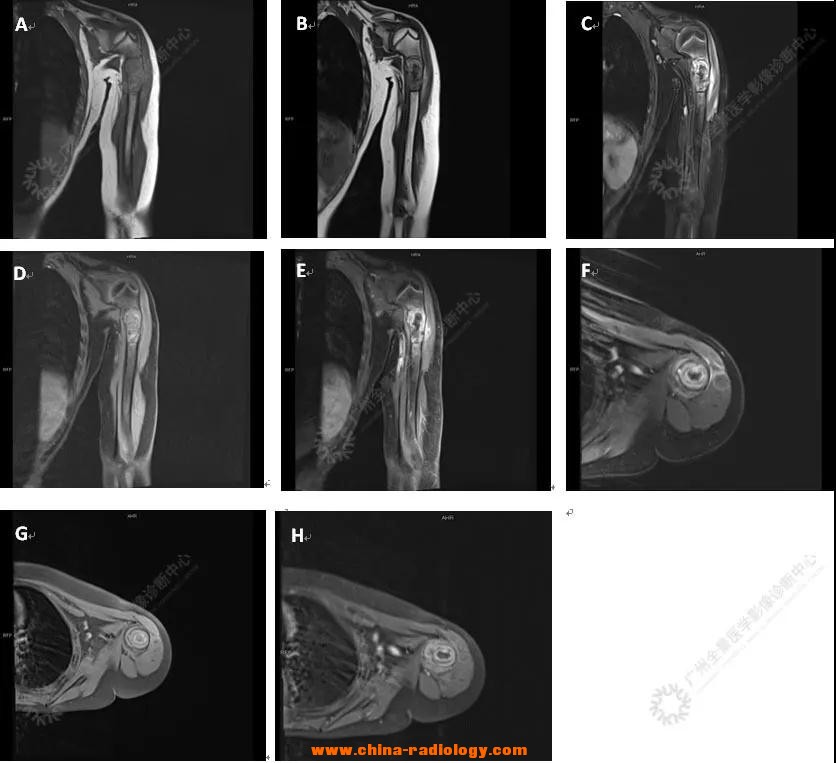

儿童导致骨折的原因-PETCT检查案···